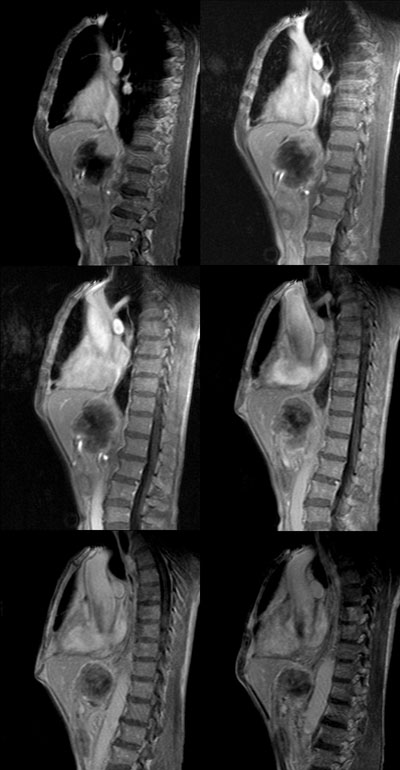

男:62岁:右上腹痛1月。b超报告肝左叶外侧段占位。请讨论灶来源!谢谢!!

肿块对周围结构是推移改变,囊变,强化不明显,不考虑来源于胰腺,后腹膜占位,期待结果

腹主动脉前肝左叶后方占位,局部与肝脂肪间隙尚存,故排除左肝来源病变.病灶主体层面位置较高,胰腺受压前移.腹腔干明显拉长包埋.增强后肿瘤边缘性强化.胃小弯侧血管明显增粗.

考虑;后腹膜来源肿瘤.神经源性肿瘤>间叶源性肿瘤>淋巴源性肿瘤.